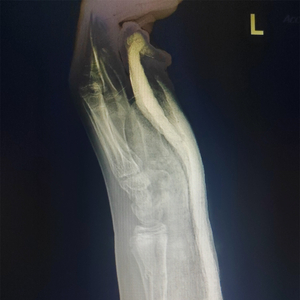

13岁的男孩小陈这几天非常苦恼,因为他的左前臂上长满了红疹。这事儿还得从一个多月前说起,那时他正和同学打闹,结果一不小心被推倒在地,单手撑地的瞬间,剧痛从腕处袭来。医院诊断结果显示:左侧桡骨中下段骨折。

检查结果出来后,医生选择保守治疗,给小陈的手腕做了传统的石膏托外固定。

小陈戴上石膏